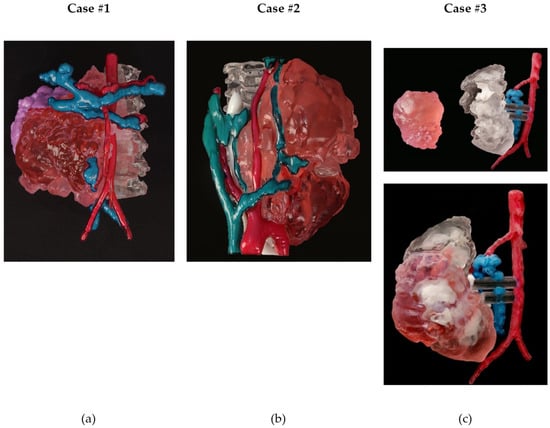

3.1.5. Three-Dimensional Printing

| 1 | Material Jetting | J5 MediJet© | 1 day 12 h 36 min | EUR 486,70 | VeroCyan™V for veins, VeroMagenta™V for arteries, Med610 for bone; tumor was printed with a combination of VeroMagenta™V + Elastico Clear with 60A shore hardness | SUP710™ (Water removable) |

| 2 | Material Jetting | J5 MediJet© | 24 h 21 min | EUR 435,51 | VeroCyan™V for veins, VeroMagenta™V for arteries, Med610 for bone, DraftWhite for airway; tumor was printed with a combination of VeroMagenta™V + Elastico Clear with 60A shore hardness | SUP710™ (Water removable) |

| 3 | Material Jetting | J5 MediJet© | 10 h 56 min | EUR 130,33 | VeroCyan™V for veins, VeroMagenta™V for arteries, Med610 for the kidney, DraftWhite for calyces; tumor was printed with a combination of VeroMagenta™V + Elastico Clear with 60A shore hardness | SUP710™ (Water removable) |